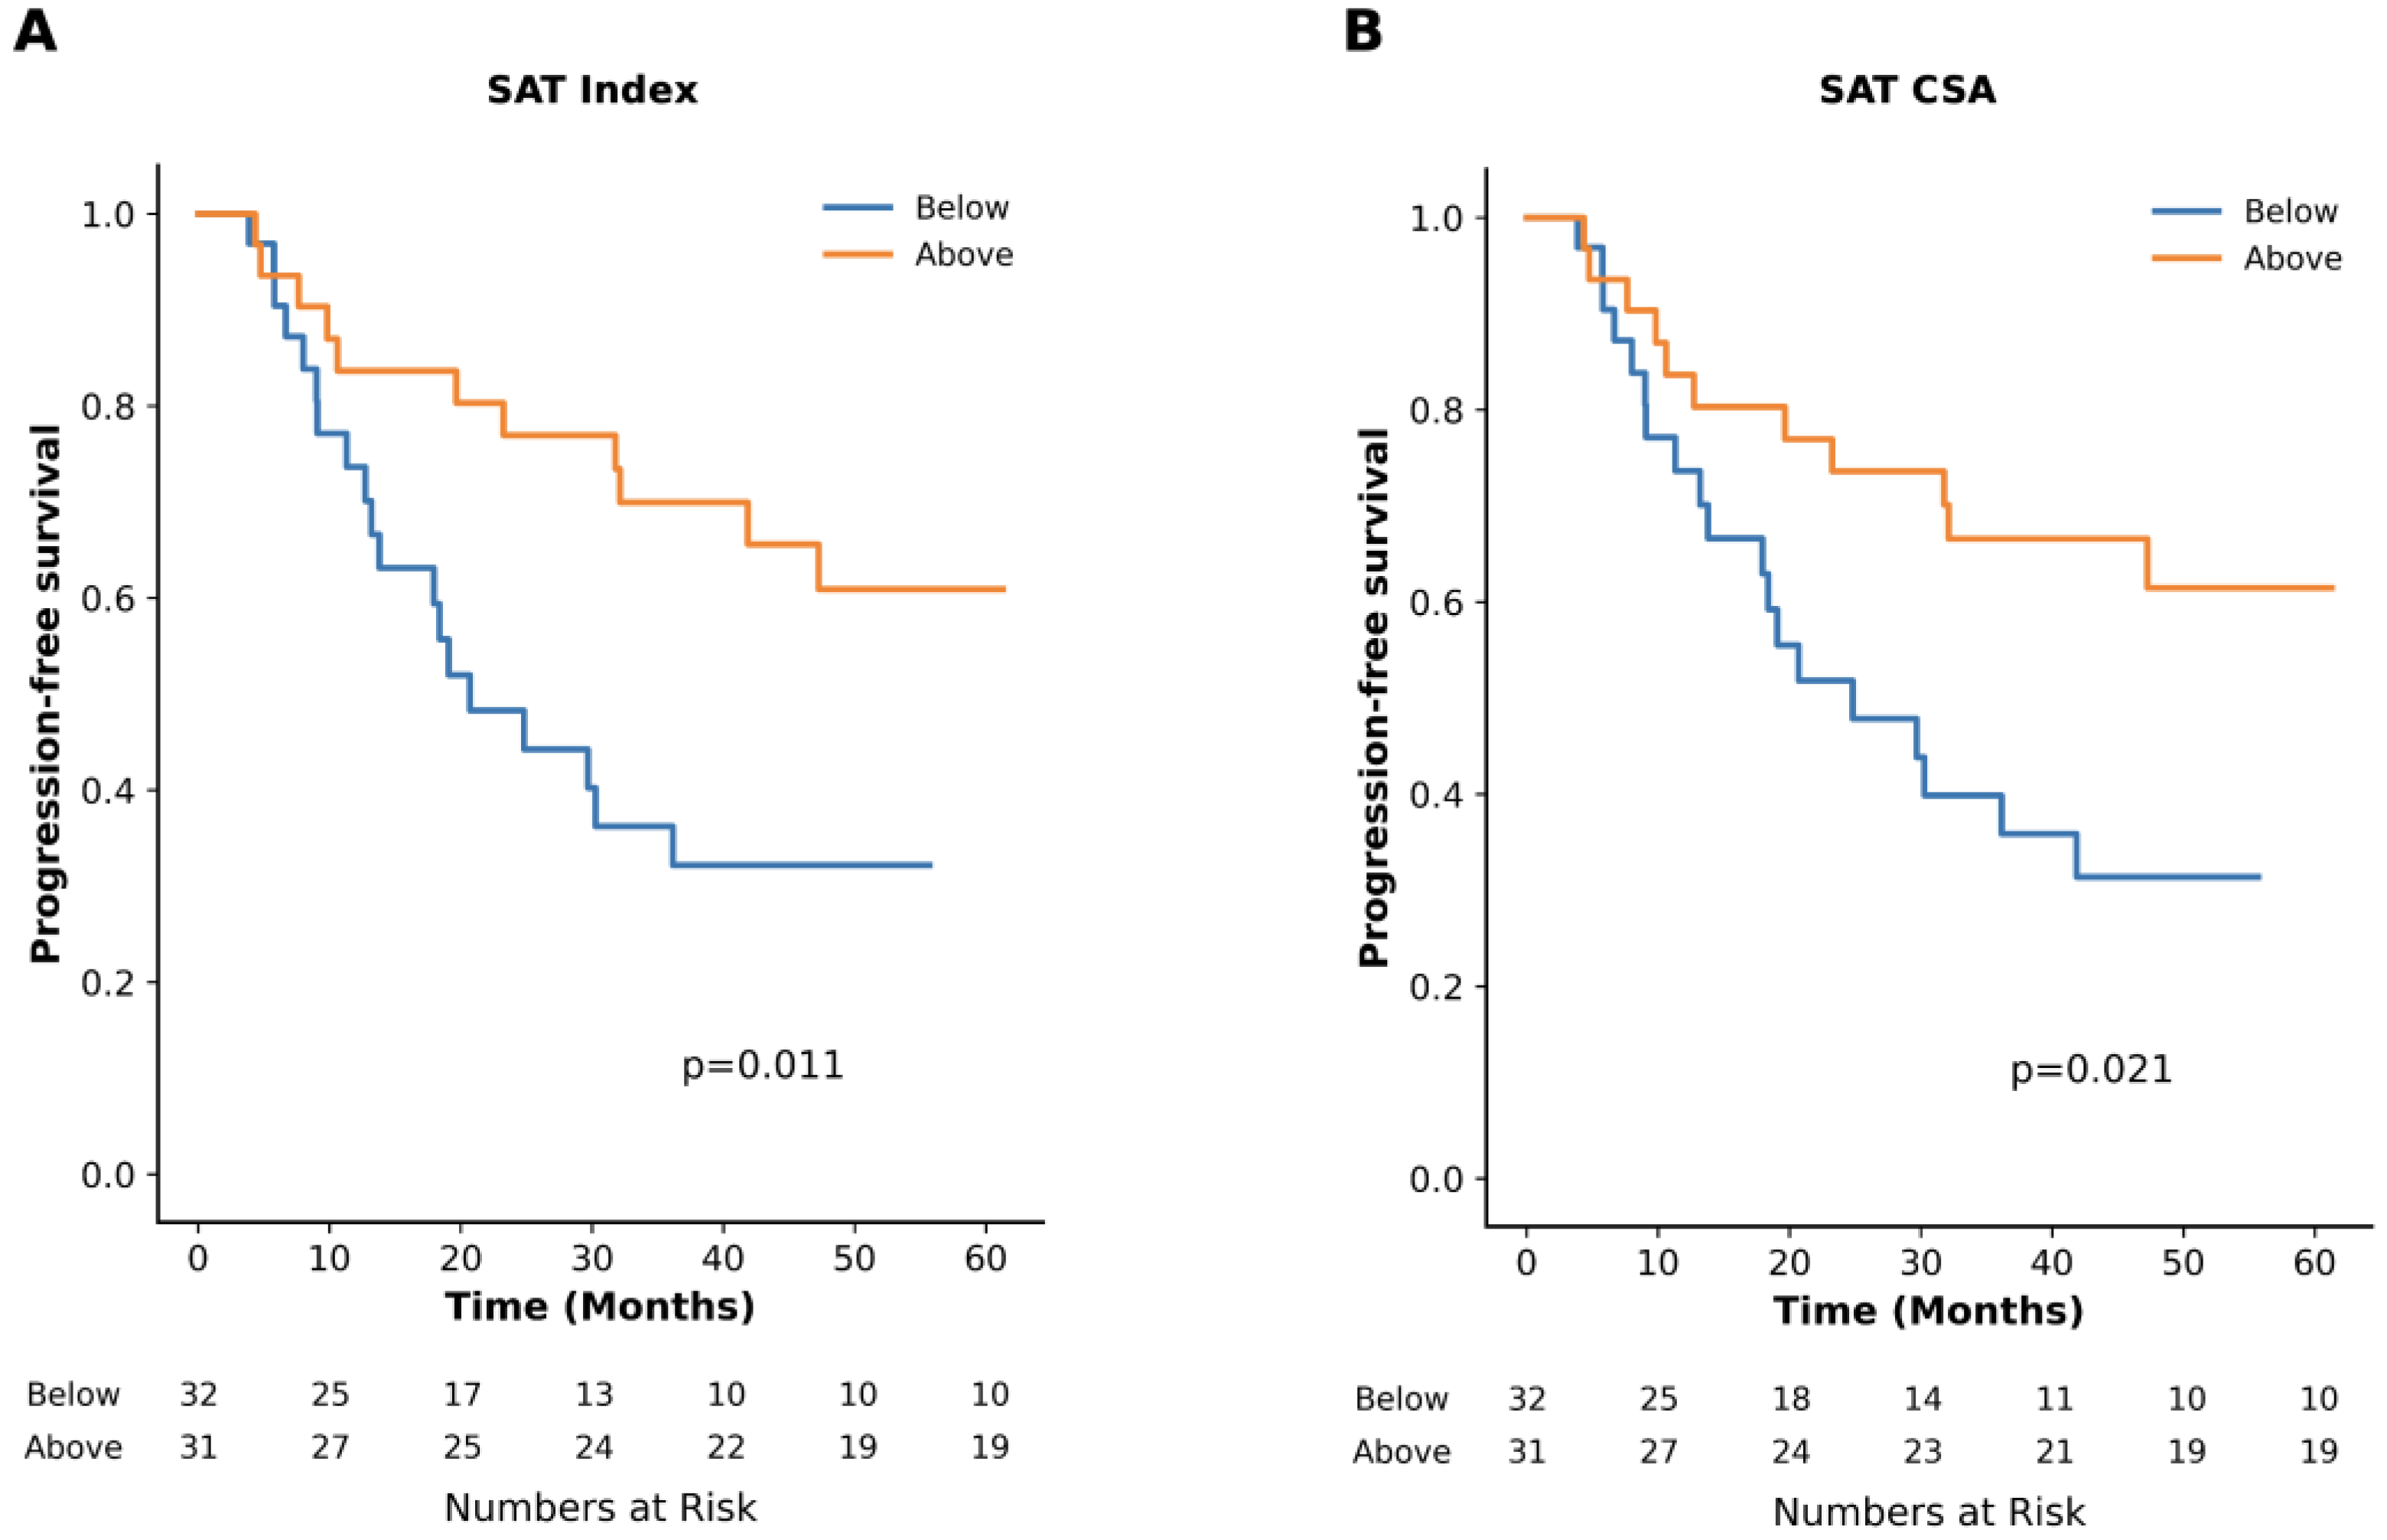

3.2. Impact of Adipose Tissue

| SAT CSA in cm2 | 213.2 (187.5, 271.1) | 273.1 (185.6, 336.2) | 24.8 (13.8–41.9) vs. NR (32.1-NR), p = 0.02 |

| SAT Index in cm2/m2 | 74.4 (63.7, 93.7) | 101.6 (72.9, 125.0) | 20.7 (13.2–36.1) vs. NR (41.9-NR), p = 0.01 |